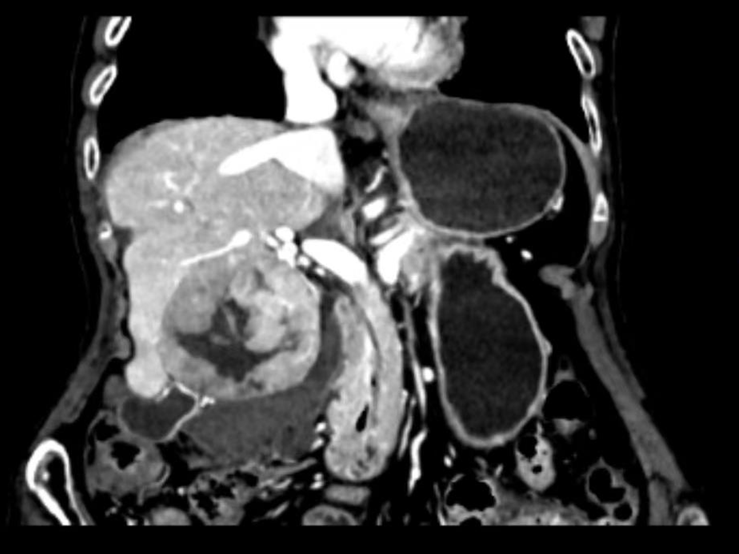

治疗前

已90岁高龄的洪老太太,被突如其来的腹部剧痛袭击,急诊入院检查发现她的肝门区有一个7.1厘米的巨大肿瘤,并不幸发生自发性破裂,导致内出血,情况十分凶险。